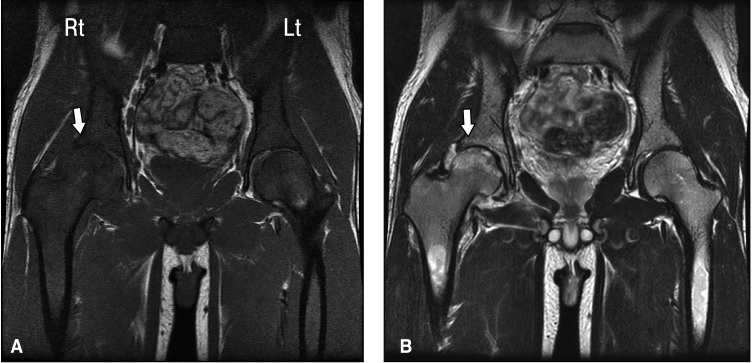

Симптомы некроза сустава

Симптомы некроза сустава могут варьироваться в зависимости от стадии заболевания, но обычно включают:

• Боль в суставе, особенно при движении.

• Ограничение подвижности сустава.

• Отечность вокруг пораженного участка.

• Изменение формы сустава.

• Возможно нагноение или покраснение кожи в области сустава.